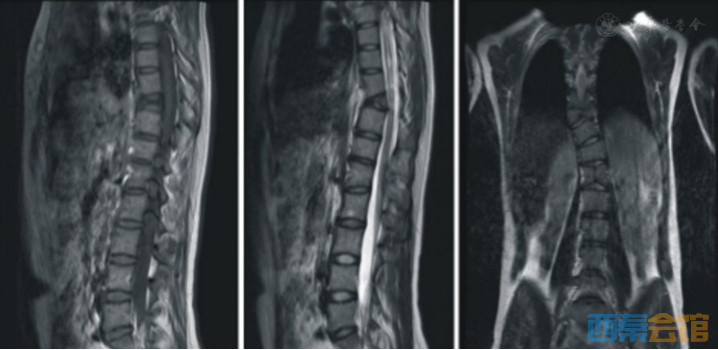

15岁女孩,显示脊柱侧弯、胸10椎体呈蝴蝶椎畸形,合并脊髓空洞改变。